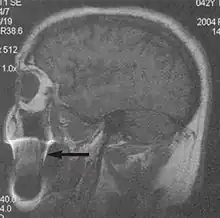

A motion artifact is one of the most common artifacts in MR imaging.[2] Motion can cause either ghost images or diffuse image noise in the phase-encoding direction. The reason for mainly affecting data sampling in the phase-encoding direction is the significant difference in the time of acquisition in the frequency- and phase-encoding directions.[1] Frequency-encoding sampling in all the rows of the matrix (128, 256 or 512) takes place during a single echo (milliseconds). Phase-encoded sampling takes several seconds, or even minutes, owing to the collection of all the k-space lines to enable Fourier analysis. Major physiological movements are of millisecond to seconds duration and thus too slow to affect frequency-encoded sampling, but they have a pronounced effect in the phase-encoding direction. Periodic movements such as cardiac movement and blood vessel or CSF pulsation cause ghost images, while non-periodic movement causes diffuse image noise (Fig. 1). Ghost image intensity increases with amplitude of movement and the signal intensity from the moving tissue. Several methods can be used to reduce motion artifacts, including patient immobilisation, cardiac and respiratory gating, signal suppression of the tissue causing the artifact, choosing the shorter dimension of the matrix as the phase-encoding direction, view-ordering or phase-reordering methods and swapping phase and frequency-encoding directions to move the artifact out of the field of interest.[1]